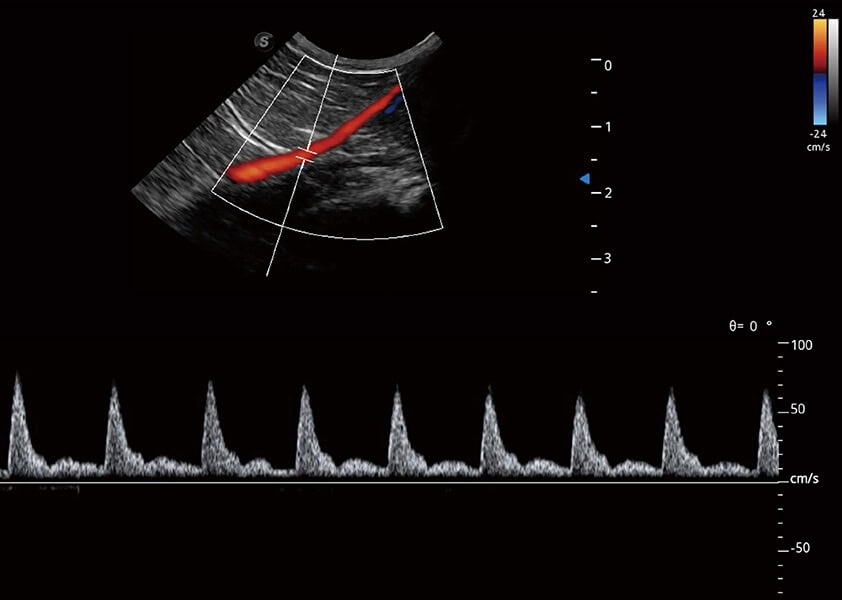

ProPet 60 作为一款高端台式动物超声设备,为动物医生的日常诊断提供了一系列贴合动物临床需求、解决临床实际问题的高级成像功能。凭借全系列高清探头,满足医生对腹部、心脏、生殖、浅表、肌骨等成像的所有需求,切实帮助您提升检查效率,提高诊断信心。

动物是人类最亲密的朋友和最值得信赖的伙伴。新葡的京集团8814检测站也一直致力于探索动物专用的超声影像解决方案。 全新推出的ProPet系列,是新葡的京集团8814检测站在动物超声影像智能化、专业化、精准化的一次跨越式革新。动物不能用言语来表述自己的不适,通过超声影像,ProPet系列搭建了动物医生与不同物种沟通的“桥梁”,为动物医生注入了“治愈之力”。